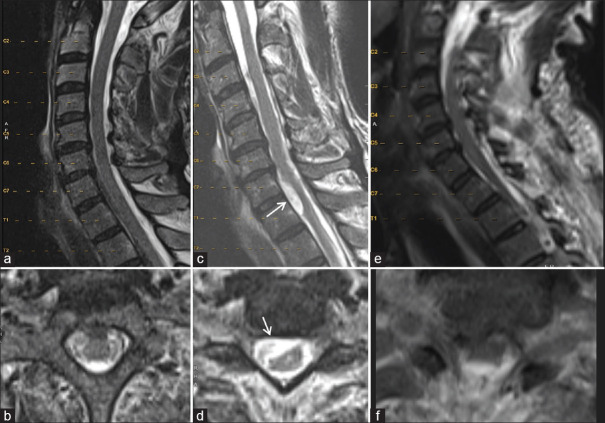

Spinal arachnoid web (AW) is a rare condition causing spinal cord-related issues. Its cause is often idiopathic but can be linked to past trauma or spine surgery. We describe two cases of AWs that developed after subarachnoid hemorrhage (SAH). Case #1 is a 71-year-old male with nonaneurysmal SAH who developed myelopathy 1 year later. Magnetic resonance imaging revealed upper thoracic cord edema and an AW. Case #2 is a 57-year-old female who underwent coiling of a ruptured basilar artery aneurysm and ventriculoperitoneal shunting for hydrocephalus. Twenty months later, she developed mid-thoracic AW requiring surgical resection. Both patients showed symptom improvement postresection avoiding further reoperation. History of SAH is emerging as a risk factor for AW development, emphasizing the importance of monitoring delayed-onset myelopathy and back pain in recent SAH patients.

脊髓蛛网膜(AW)是一种罕见的疾病,会引起脊髓相关问题。其病因通常是特发性的,但也可能与过去的创伤或脊柱手术有关。我们描述了两例在蛛网膜下腔出血(SAH)后出现的蛛网膜瘤。病例1是一名71岁的男性,患有非动脉瘤性SAH,1年后出现脊髓病变。磁共振成像显示上胸段脊髓水肿和 AW。病例 2 是一名 57 岁的女性,因脑积水接受了基底动脉瘤破裂的盘绕手术和脑室腹腔分流术。20 个月后,她患上了中胸 AW,需要进行手术切除。两名患者在切除术后症状均有所改善,避免了再次手术。SAH史正在成为AW发病的一个危险因素,这强调了监测近期SAH患者迟发性脊髓病和背痛的重要性。